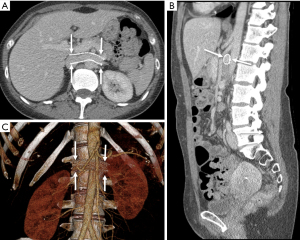

Extrinsic to the kidney, the LRV communicates most directly with the lumbar venous plexus and the left gonadal vein [in addition to the inferior vena cava (IVC)] (Figure 2), which frequently dilate as they emerge as preferential drainage pathways for the renal vein (Figure 3A) (11). In advanced cases, gonadal vein engorgement can progress to pelvic congestion syndrome (25), a condition defined as noncyclic chronic pelvic pain and/or heaviness attributable to gonadal vein reflux and dilation (Figure 3B) (26). The gonadal vein communicates directly with the ovarian venous plexus and subsequently the uterine venous plexus, eventually draining to the hypogastric vein via visceral tributaries or parietal tributaries via gluteal vulvoperineal veins—any of which may contribute to pain, fullness, or discomfort in the pelvis (27). Concomitant NCS has been described in up to 18% of patients with pelvic venous congestion syndrome (28). In males, NCS, as diagnosed by elevated LRV velocities, is frequently associated with varicocele caused by venous hypertension and collateralization (Figure 3C) (29).

MRI is particularly beneficial in children and adolescents owing to the absence of radiation while retaining the ability to evaluate adjacent abnormal vascular structures, such as an enlarged gonadal vein (40). Vein diameter ratios and “beak sign” can be evaluated in similar fashion as CT (Figure 6). A comparison of various MRI sequences determined that True Fast Imaging with Steady-State Free Precession (T2-TRUFI) has particularly good image quality for evaluating the LRV (41). High signal intensity in the LRV on fast-spin-echo T2-weighted sequence due to venous hypertension and stagnation may be particularly useful for diagnosis and evaluating response to therapy (42).